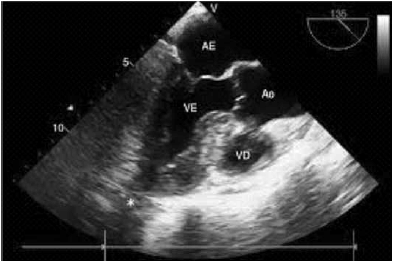

Paciente do sexo feminino, 72 anos, portadora de mieloma múltiplo em investigação atual. Com internação via pronto-socorro, após terceira ida nos últimos meses, pela mesma história de tosse seca, dispneia ao repouso e edema de membros inferiores. Ao exame físico, apresenta hipofonese de bulhas e presença de terceira bulha, com queda da pressão arterial sistólica de 15 mmHg durante a inspiração profunda; estertores crepitantes nos dois terços inferiores dos pulmões. O eletrocardiograma de repouso com padrão de baixa voltagem e sem sinais de sobrecarga de câmaras esquerdas e o ecocardiograma realizado à beira a leito, na UTI, é o que segue:

O tratamento de escolha diante desse quadro clinico é:

A etologia que deve ser pesquisada para o quadro clínico?

A hipótese diagnóstica compatível com o quadro clínico é: